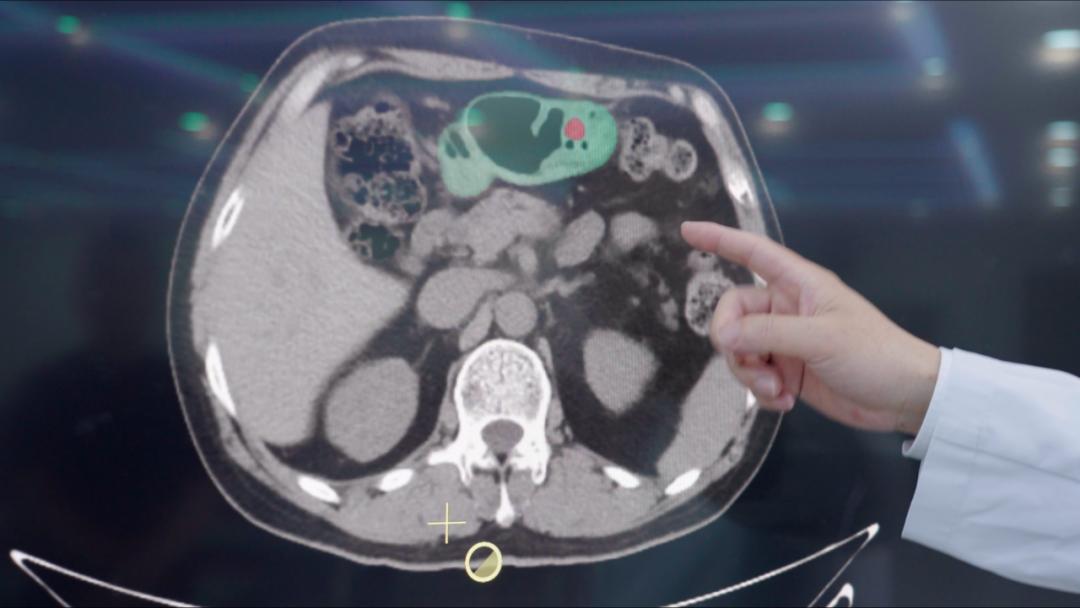

该AI模型具体应用于“平扫CT” AI在临床医学模式上,首先用AI对腹部平扫CT进行初步筛查,然后通过胃镜对AI提示的胃癌高危人群进行诊断。